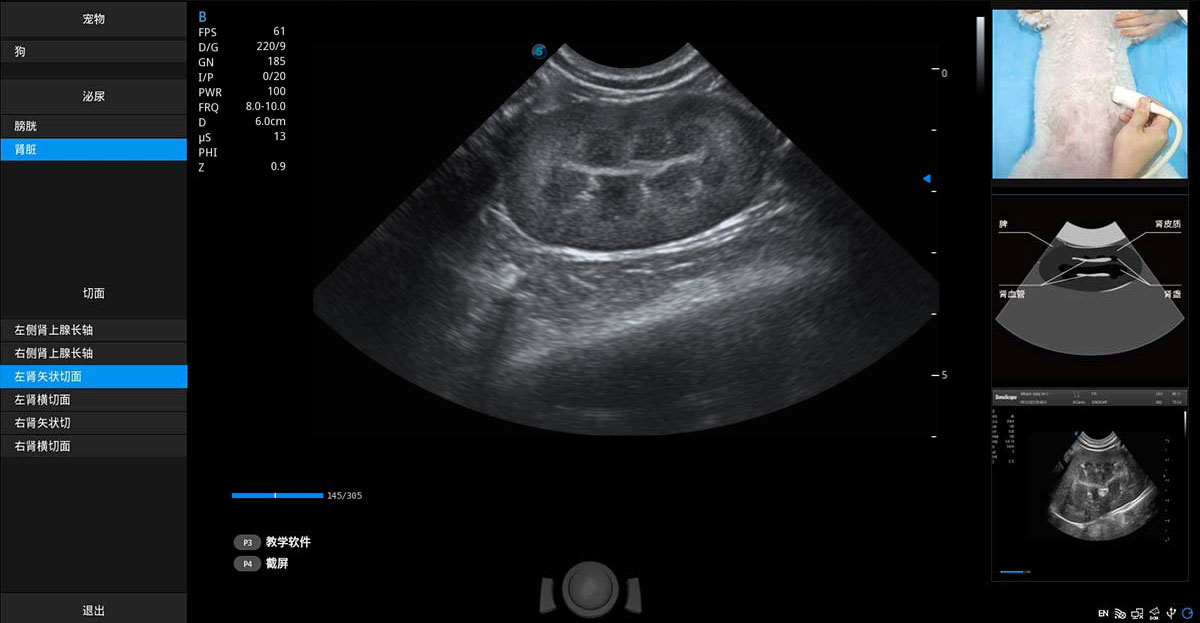

ProPet 70專(zhuān)為動(dòng)物醫(yī)生設(shè)計(jì),對(duì)不同的動(dòng)物體型和生理結(jié)構(gòu)作出了針對(duì)性的優(yōu)化。通過(guò)動(dòng)物影像專(zhuān)用軟件,可滿足個(gè)性化的應(yīng)用需求,幫助動(dòng)物醫(yī)生獲得更精確的診斷數(shù)據(jù)。

提供解剖示意圖、標(biāo)準(zhǔn)超聲圖像、掃查手法圖和操作者實(shí)時(shí)檢查圖像,指導(dǎo)操作者進(jìn)行標(biāo)準(zhǔn)切面的正確掃查。

針對(duì)寵物、馬科、農(nóng)場(chǎng)動(dòng)物、實(shí)驗(yàn)室動(dòng)物和異寵等20多種動(dòng)物種類(lèi),預(yù)置豐富的動(dòng)物注釋及動(dòng)物體標(biāo)庫(kù)。